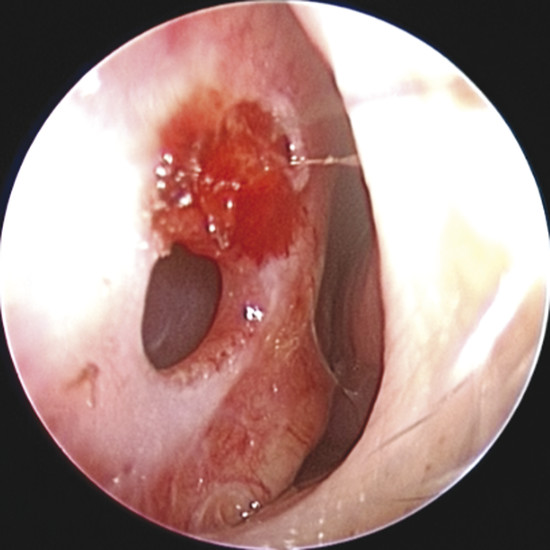

Upon physical examination of the nose, a full diagnosis cannot be made until all crusts have been removed and decongestion of the turbinates has taken place, making it possible to visualize the entire nasal septum. The nasal endoscopy allows appreciating the configuration of the NSP, the presence or absence of adherent crusts on the edges of the defect (Fig. 6‑1), any easily bleeding areas (Fig. 6‑2), and the state of the remaining mucosa, which may present some aspects regarding ischemic conditions (cocaine abuse) (Fig. 6‑3).